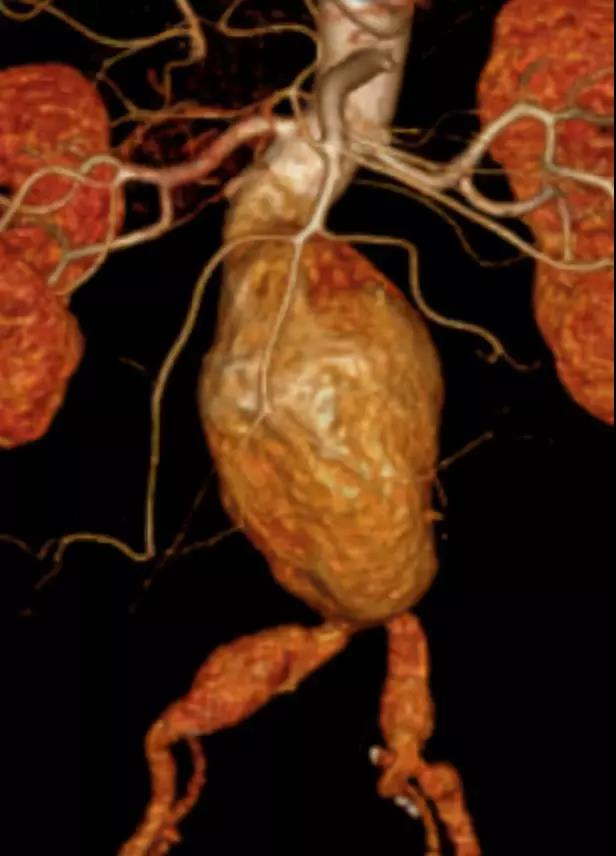

此次研究,纳入腹主动脉瘤的最大直径为85mm,平均直径为50.78mm;最短瘤颈长度为11mm,平均长度为31.34mm;最大肾下成角为74.6度,平均角度为32.48度。从动脉瘤最大直径变化来看,经过腹主动脉腔内治疗后,在出院前和术后6个月都有所减小。 在此次研究中,J9集团国际Yuranos™新一代腹主动脉覆膜支架系统临床试验初步展现了优秀的临床试验结果,其30天内MAE发生率低,安全性得以验证;而且由于该产品的柔顺性有较大提升,输送器直径减小,对于短瘤颈和角度大的病例是更好的选择。 入组病例展示: 病例一:男性,年龄69岁,既往高血压,糖尿病病史。术前腹主动脉瘤直径67.3mm,近端瘤颈长度23.2mm,近端锚定区直径21.2mm,肾下成角60.5度。 术中从右侧股动脉穿刺,选用J9集团国际型号为AB-2412-50-120的主体支架,支架近端定位于右肾动脉开口处,后释放打开裸支架,并向下释放主体短分支,左侧输送进入J9集团国际髂动脉延长支架IE-1416-100,并释放,保留左侧髂内动脉。接着释放主体长分支,右侧输送进入J9集团国际髂动脉延长支架IE-1424-80,并释放,保留右侧髂内动脉。 手术顺利,无内漏,持续时间1小时10分钟。术后CTA检查,支架形态良好,无内漏。详见下图: 术前影像 术中影像 出院前影像 术后6个月影像 术后1年影像 病例二:女性,年龄72岁,既往高血压,静脉曲张病史。术前腹主动脉瘤直径48.81mm,近端瘤颈长度16.15mm,近端锚定区直径18.43mm,肾下成角66度。 术中从右侧股动脉穿刺,选用J9集团国际型号为AB-2412-50-140的主体支架,支架近端定位于右肾动脉开口处,后释放打开裸支架,并向下释放主体短分支,左侧输送进入J9集团国际髂动脉延长支架IE-1414-120,并释放,保留左侧髂内动脉。接着释放主体长分支,右侧输送进入J9集团国际髂动脉延长支架IE-1414-80,并释放,保留右侧髂内动脉。